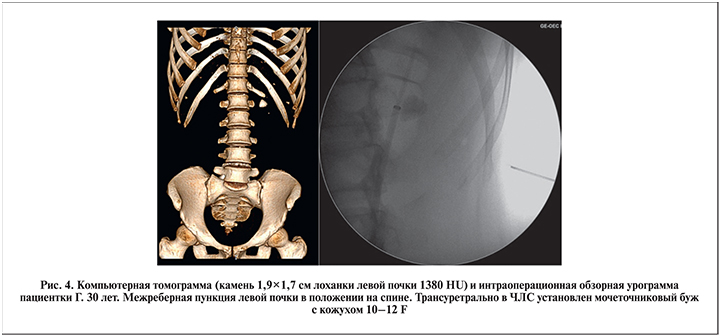

На предварительном этапе всем пациентам осуществляли уретроцистоскопию, катетеризацию почки со стороны предполагаемого оперативного вмешательства. С целью пассивной эвакуации фрагментов конкремента в процессе дробления большинству пациентов с размером камня более 1,5 см, а также ряду престентированных больных под рентгентелевизионным контролем предварительно устанавливали мочеточниковый кожух диаметром 10–12 F по струне-проводнику (рис. 1). Всего мочеточниковый кожух был установлен 42 (56,7%) пациентам. В остальных наблюдениях катетеризацию почки проводили мочеточниковым катетером либо наружным стентом диаметром 5–7 F. Трансуретральная катетеризация почки давала возможность интраоперационного контрастирования и при необходимости – дилатации ЧЛС для прицельной пункции почки, предотвращала миграцию крупных фрагментов конкремента в мочеточник, а также позволяла отмывать мелкие фрагменты камня (до 3 мм) через мочеточниковый кожух.

Пункцию почки осуществляли под совмещенным рентгентелевизионным (ультразвуковым) и прямым эндоскопическим контролем. При этом к пункционной игле с рабочим тубусом 4,85 F напрямую присоединяли оптическую и ирригационную системы. Учитывая ограниченные возможности в манипулировании внутри почки полужестким инструментом диаметром 4,85 F, доступ по возможности формировали непосредственно на камень (высокая хрупкость оптики!). Сочетанная эндоскопическая визуализация с рентгеновским или ультразвуковым наведением позволяла оптимально создавать пункционный доступ для нефроскопического этапа. Достоверным признаком адекватной пункции было поступление мочи по внутреннему просвету иглы, а также собственно визуализация слизистой ЧЛС или камня. Если принималось решение об использовании тубуса 8 F (обычно в ситуациях, когда требовался нефроскопический осмотр чашечек, расположенных под углом к пункционному доступу), в ЧЛС проводили струну-проводник типа Лундерквист с прямым или изогнутым наконечником, по которой осуществляли бужирование пункционного хода до 8 F. После экстракции иглы к тубусу инструмента присоединяли специальный трехпортовый адаптер для подключения ирригационной трубки и проведения лазерного волокна и оптики. Учитывая необходимость активного маневрирования инструментом внутри собирательной системы почки, при камнях размером более 1,5 см в качестве рабочего тубуса чаще использовали более ригидный тубус размером 8 F (рис. 4–6).

В нашем исследовании у 37,9% пациентов имели место камни размером более 1,5 см. Для достижения максимального эффекта литотрипсии данной категории пациентов предварительно трансуретрально устанавливали мочеточниковый кожух размером 10–12 F, по которому фрагменты конкремента пассивно эвакуировались в ходе дробления. В литературе очень мало указаний на использование мочеточниковых кожухов в ходе микро-ПНЛ [21]. В то же время выполнение нефроскопии через тубус 8 F вместе с использованием мочеточниковых кожухов позволило достичь полного очищения почки от конкрементов у 82,4% пациентов с крупными камнями почек.